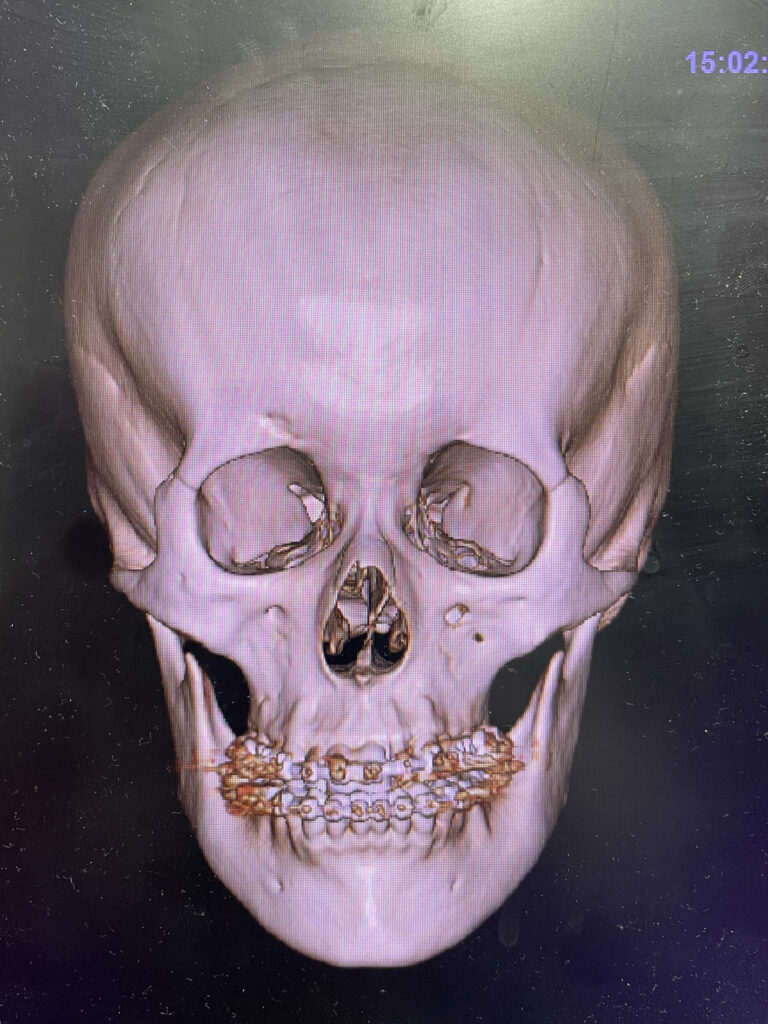

手術:上顎ルフォー1型骨切り+下顎SSRO+中抜きオトガイ形成

ほぼ予定通りの手術が行われました。